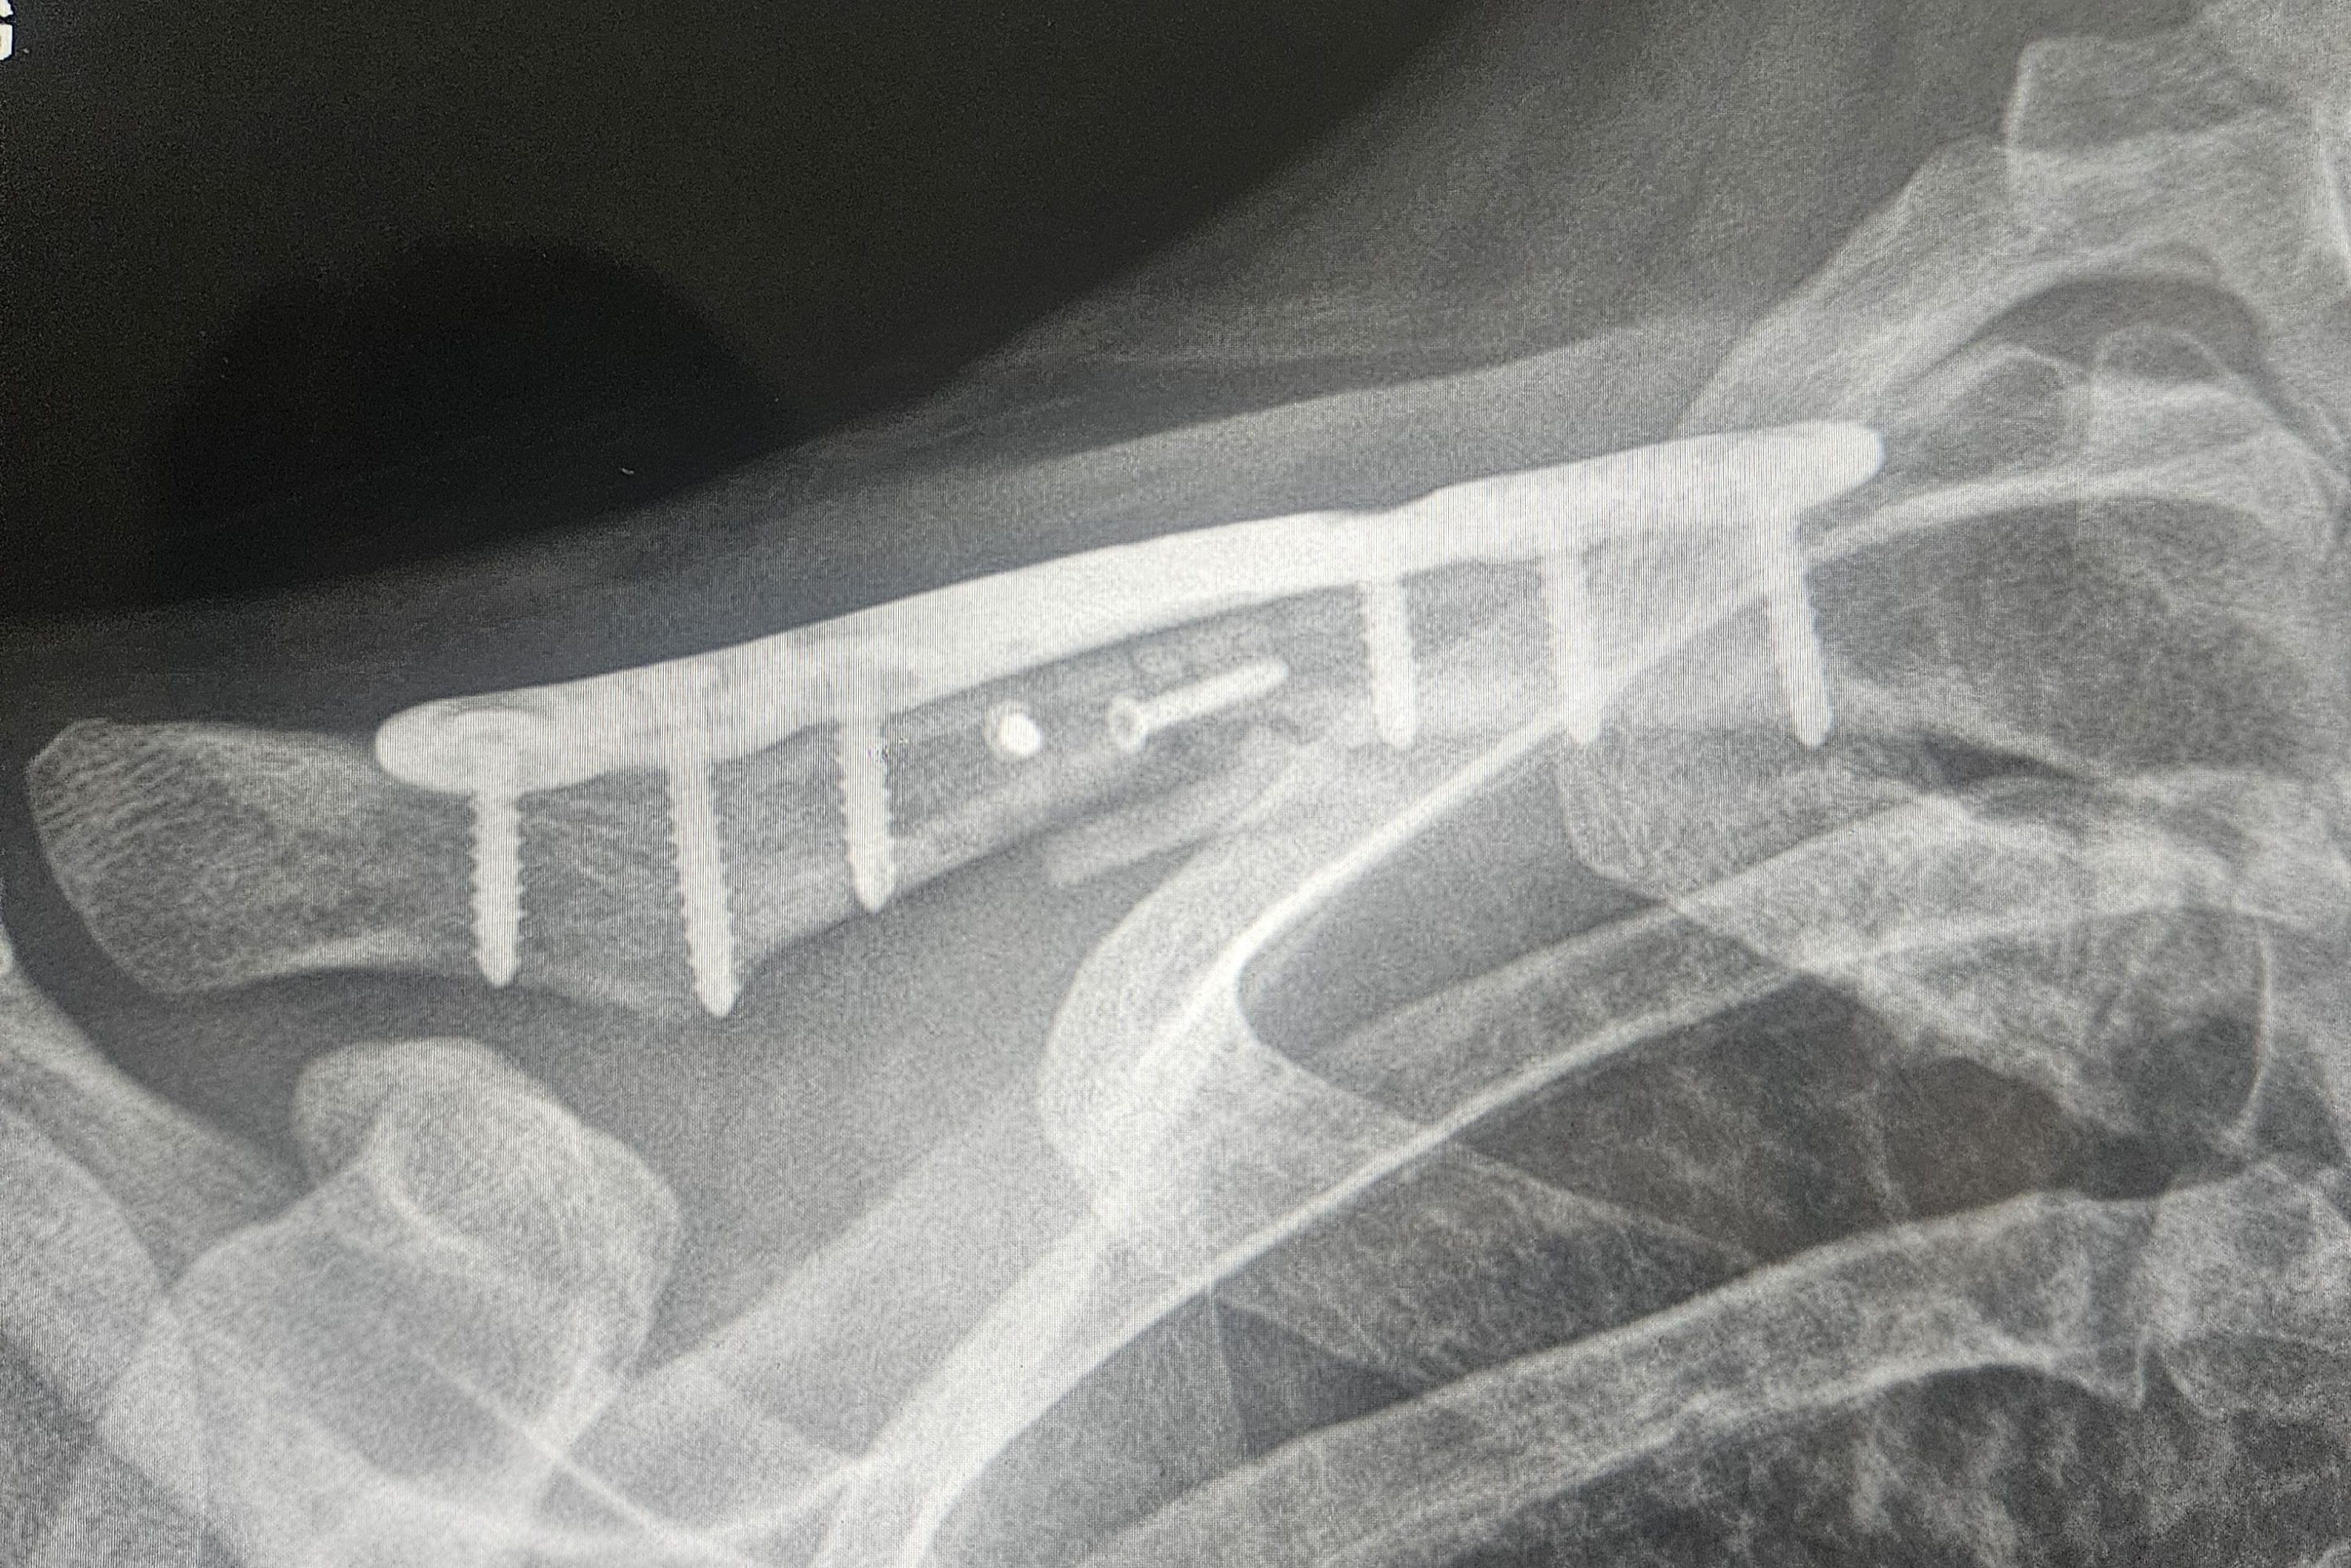

I was taken out of the trauma bay and wheeled to a small curtained room awaiting an inpatient bed. I had no concept of time. I’m not sure if I slept. It was dark. Kevin was there or he wasn’t. The patient next to me was coughing a lot. I remember thinking I hope I don’t get sick being next door to this patient. He was later discharged. My first visitor appeared early in the morning. Around my curtain appeared Brian, an anesthesiologist I knew from work and also a cycling friend. Word of my crash travelled fast. Turns out Brian was way less excited to see me as I was to see him. This wasn’t a social visit, I was his patient. That’s when I learned I would need surgery to repair my broken clavicle. Next to appear was my good friend Lindsay who also happened to be a CRNA at the hospital. She was off that day but graciously dedicated her time to help coordinate basically my entire hospital stay (forever grateful to have her as a friend). I was surprised by the next team who appeared at my bedside, Thoracic Surgery. They recommended plating some of my ribs. My drugged and concussed mind was shocked at this recommendation but they felt surgery was necessary given my arm instability and the displacement of the ribs. Honestly, I ended up moving forward with the surgery because the idea of being under anesthesia was lovely compared to the discomfort I was in awake. I was taken to the OR that afternoon.

Day three of my hospital stay was my clavicle repair surgery. My top tier anesthesia team, Brian and Lindsay, were ready to put me under for round two. I was taken to the OR where I’m pretty sure I fell asleep before they even placed me on the OR table. I don’t recall very much beyond that point. After surgery, I was taken back to the same room I came from. The rest of the day was pretty blurry after my second round of anesthesia. My trauma buddy Sam was admitted to the same unit awaiting surgery on his ankle. He was wheelchaired to my room that evening to visit. I was so happy to see him doing well but was too drowsy to stay awake for long. He did explain that he wasn’t moving at the scene of the accident to avoid the immense pain from his ankle fracture. He had his ankle operated on the day after I was discharged. Sam and I continue to send “happy crash-iversary” texts.

Five months of PT left me at about 95% recovered in terms of strength. My right shoulder soreness stuck around for a while as did the occasional zap of a nerve that was a casualty of the accident. I experience popping, “gristly” sensations in the muscles of my right rib cage/scapula. My incisions are well healed only leaving behind reddish hued scars. The silhouette of the titanium plate supporting my clavicle is visible since the swelling resolved but it isn’t too disfiguring. It took until mid-November (7 months) for my concussion symptoms to resolve. At that time, the riding season had pretty much come to an end.